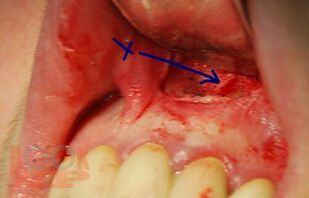

В учебном пособии на современном уровне освещены показания, противопоказания, техника выполнения зубосохраняющих операций при лечении хронических периодонтитов, а также методы предоперационной подготовки больных к хирургическому вмешательству и их послеоперационному ведению.